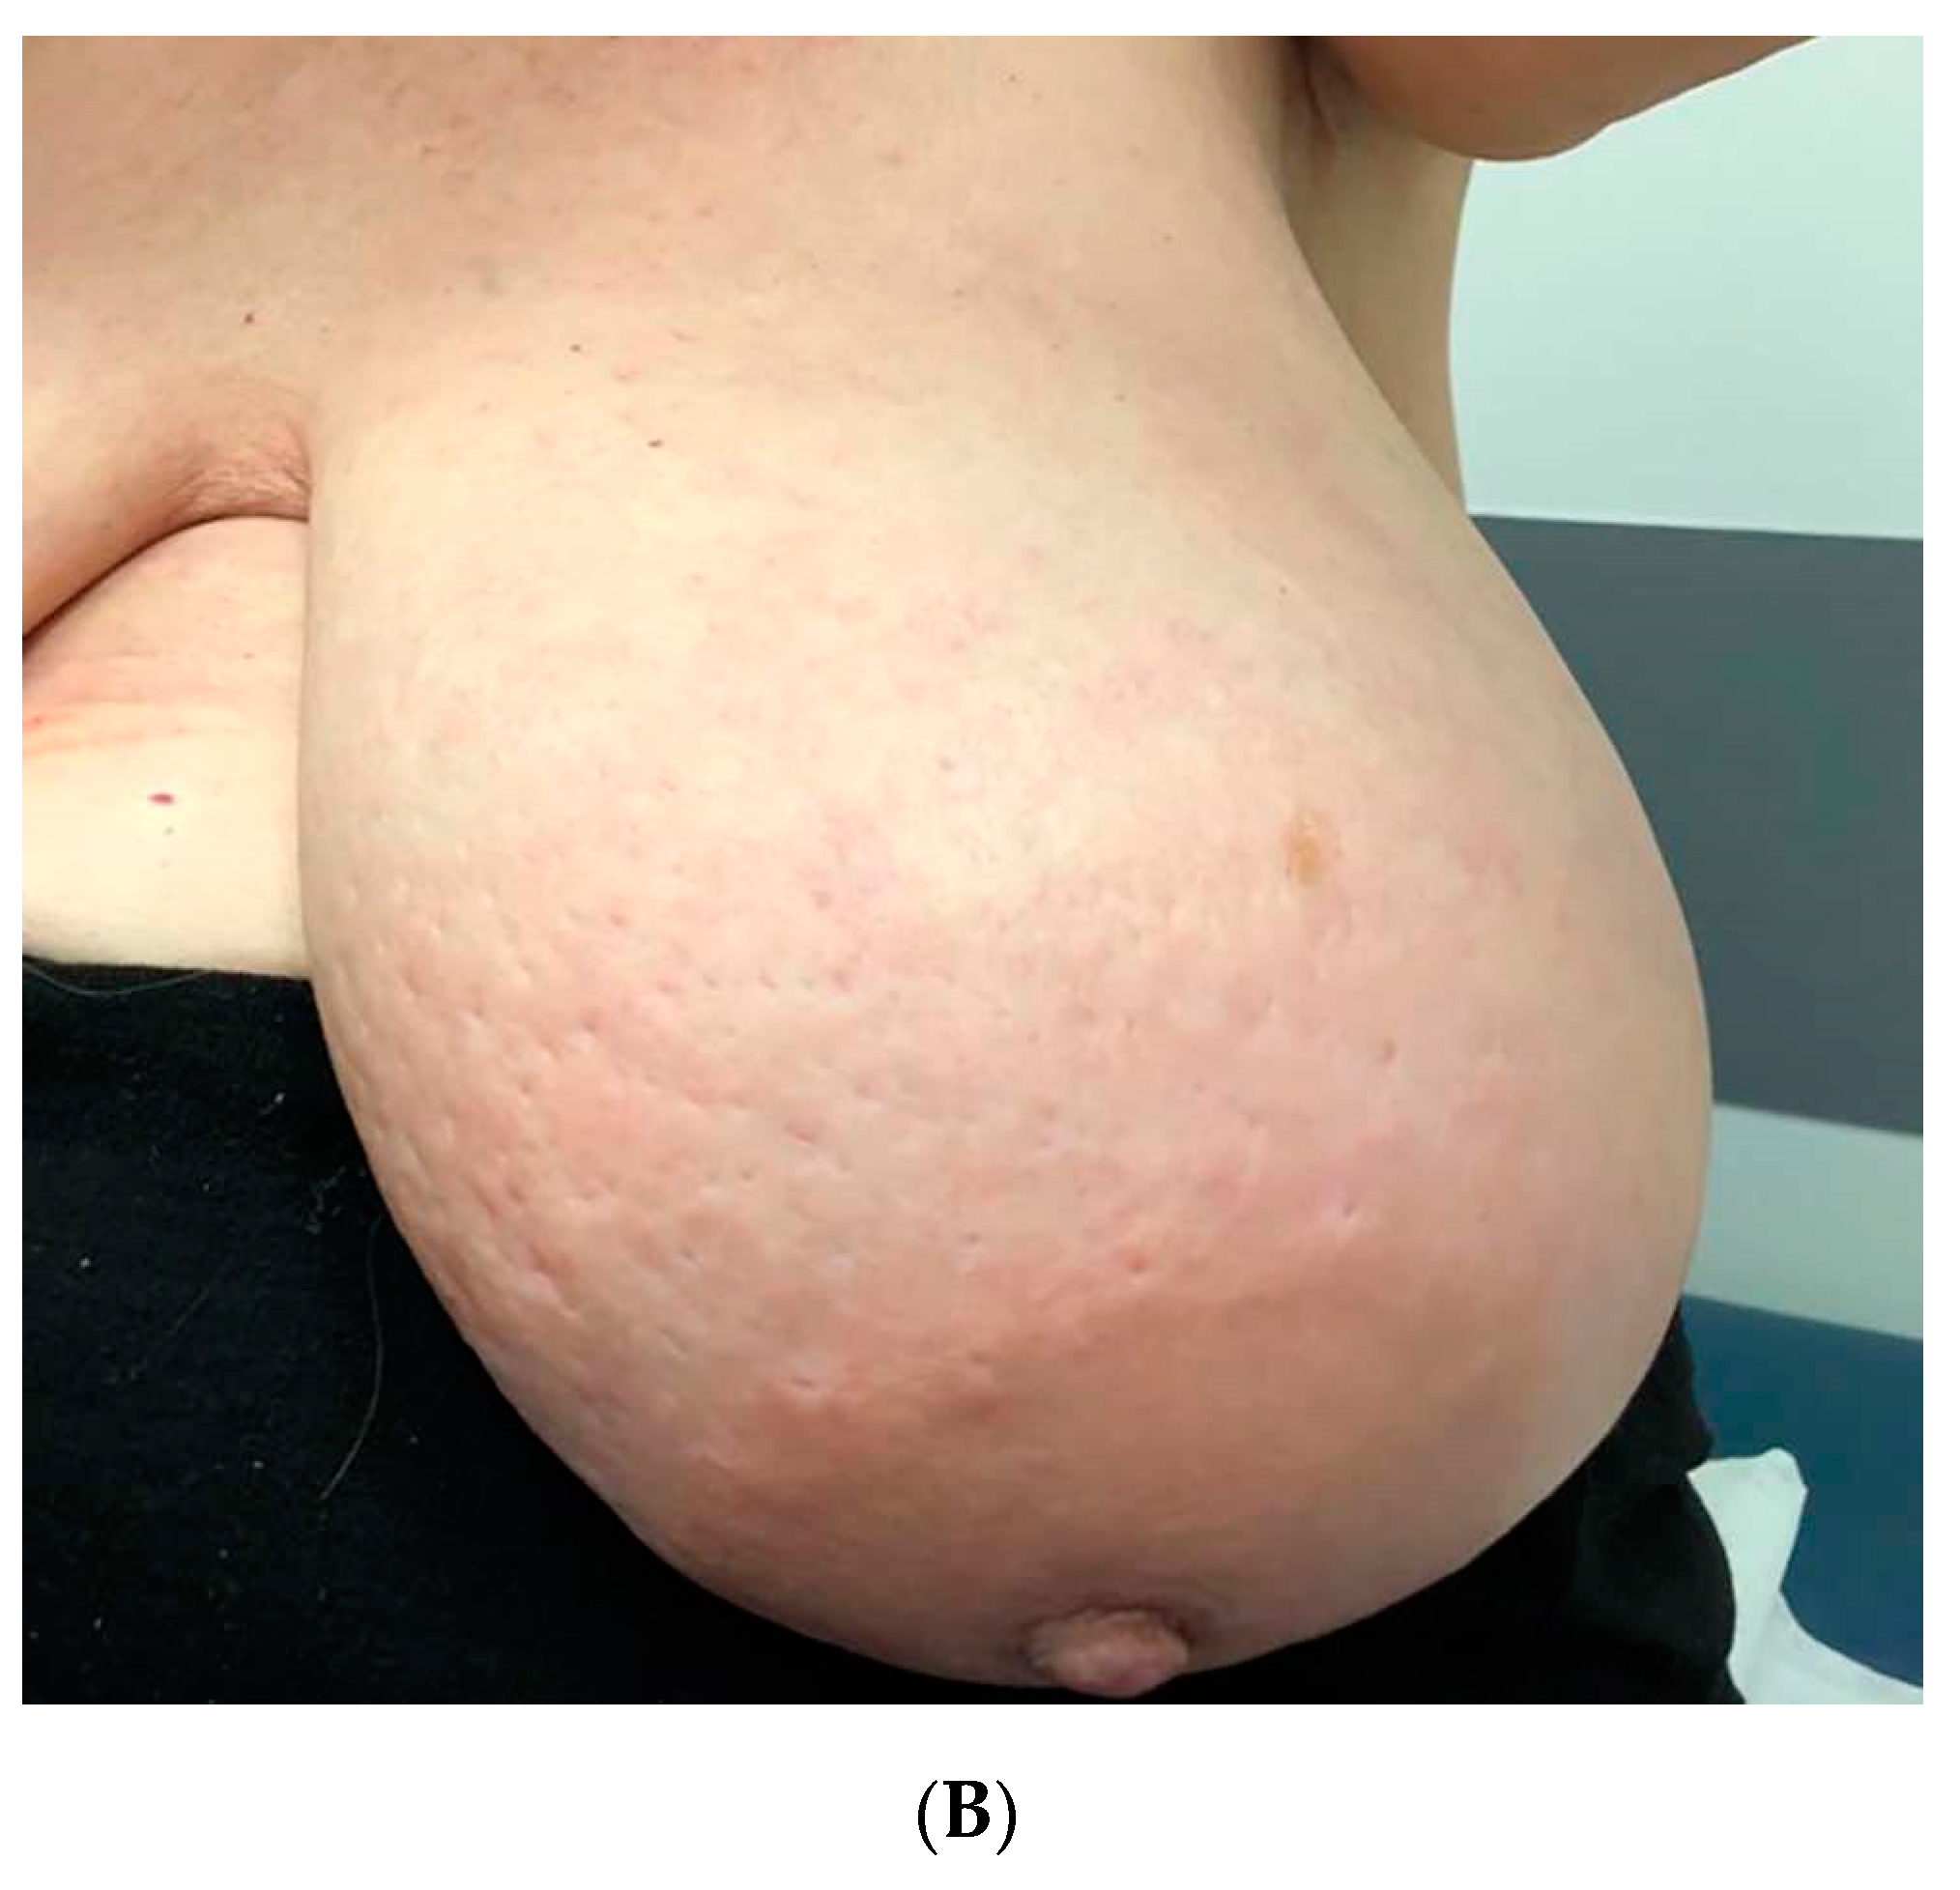

:1. Introduction

2. Case Presentation Section

2.1. Clinical History

2.2. Symptoms and Duration

2.3. Clinical Examination and Initial Assessment